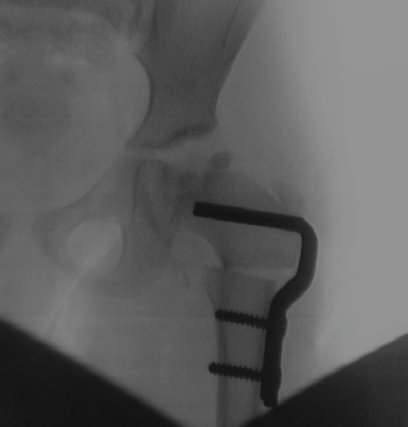

Das Röntgenbild hier zeigt übrigens, wie Emmas Oberschenkel heute aussieht. Der Oberschenkelknochen wurde durchtrennt, nach innen gekippt und mit einem Metallwinkel stabilisiert.

Ich kläre das mal eben auf: eine Ischämie ist allgemein eine Durchblutungsstörung. Und unter Femur versteht der Fachmann den Oberschenkelknochen. Bei der besagten Femurkopfepiphyse handelt es sich um nichts weniger als die Kugel des Hüftgelenks. Und die IVO ist schließlich eine Operation, bei der die Kugel per Durchtrennung des Oberschenkelknochens anders positioniert wird. Man spricht deshalb auch des öfteren von einer Umstellungsosteotomie, wobei eine Osteotomie wieder allgemein “mechanische Arbeit am Knochen” ist.